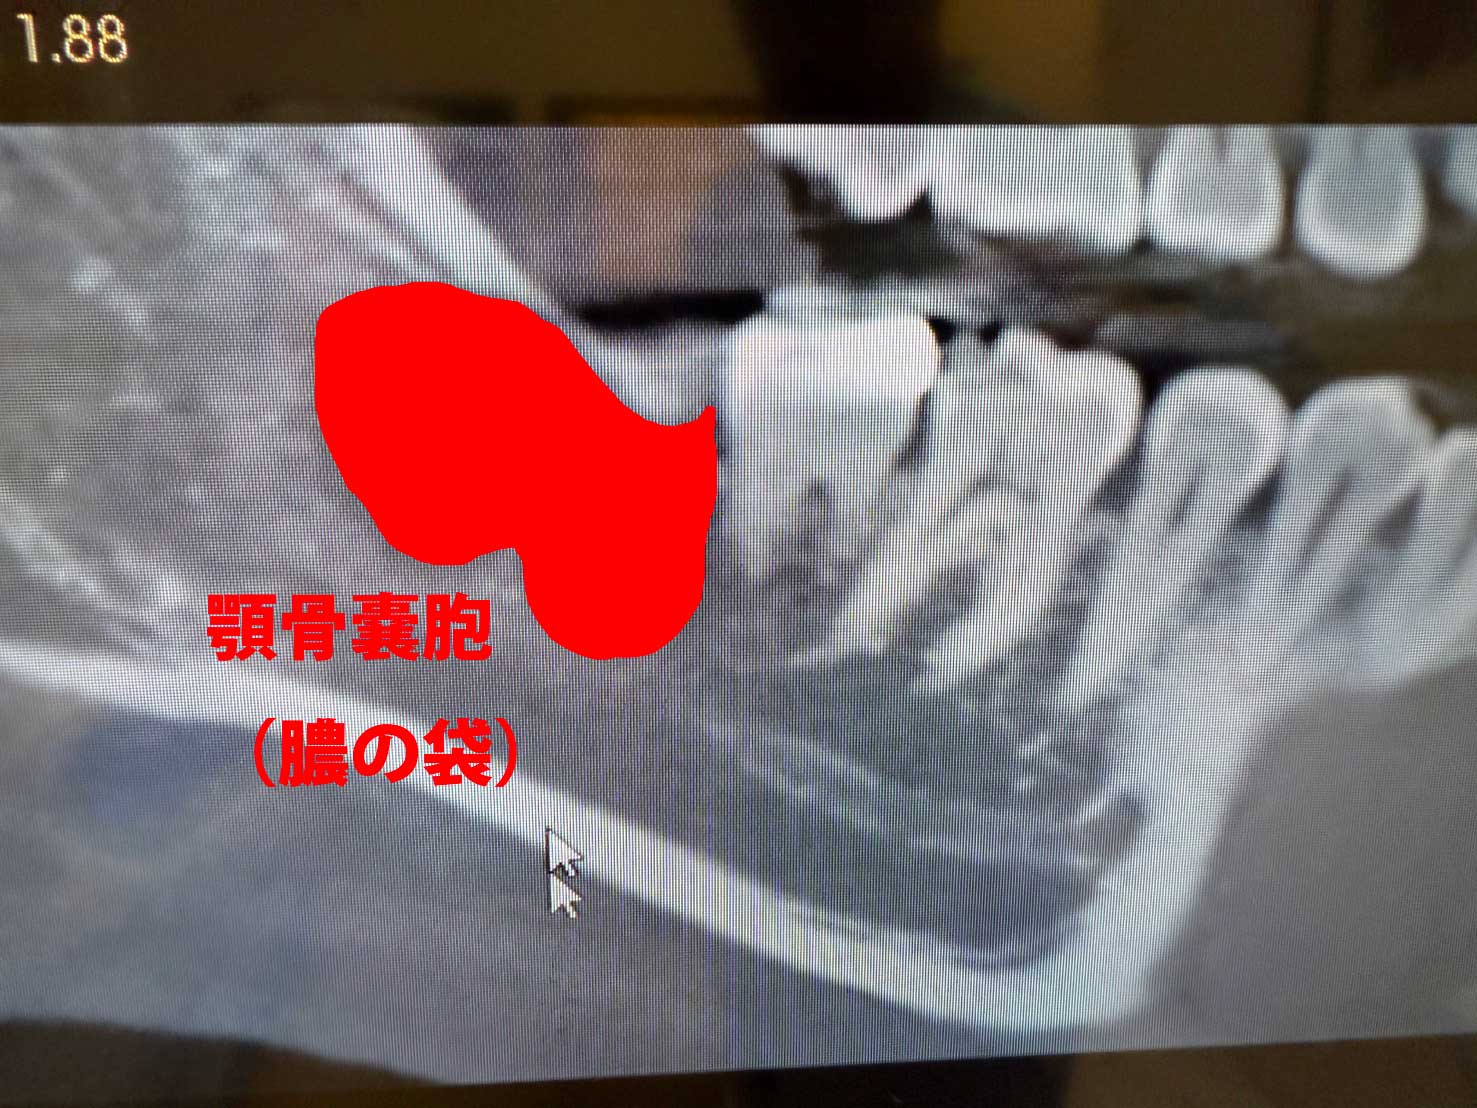

この患者さまは、親知らずに痛みがあり来院されました。こちらがCT撮影をした結果です。親知らずの横の下顎の骨の中に大きな膿の袋、嚢胞が形成されています。

X線、CTスキャン撮影の画像診断で嚢胞の正確な位置や大きさを特定し、嚢胞が周囲の骨や歯に与える影響を確認します。また歯の治療歴や外傷、や副鼻腔炎の治療歴なども詳細に確認します。そのうえで、治療計画をたてていきます。